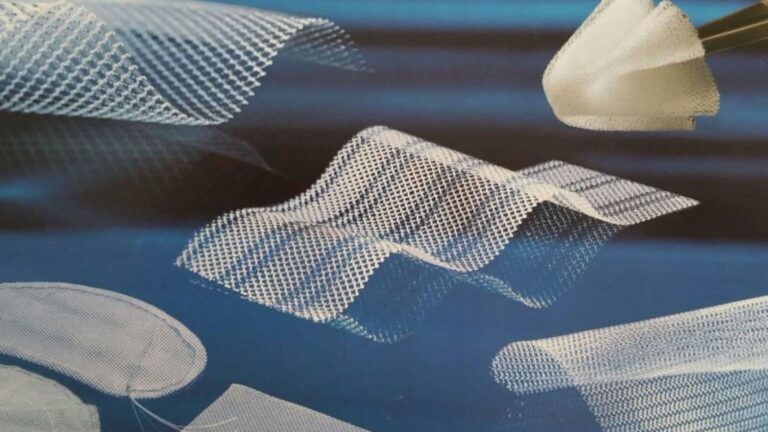

Descubre todo sobre la recuperación de una malla abdominal. Tiempos de sanación, cuidados postoperatorios, dieta,...